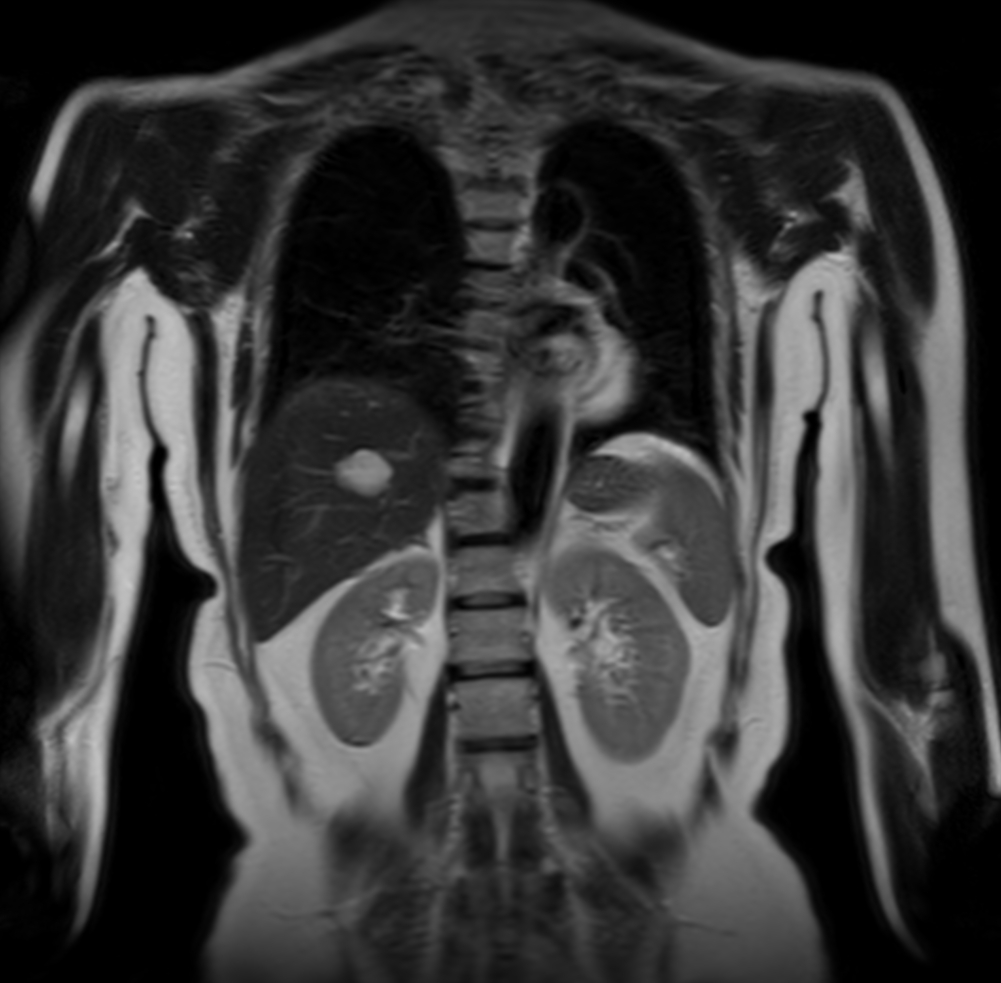

Coronal T2w SSh